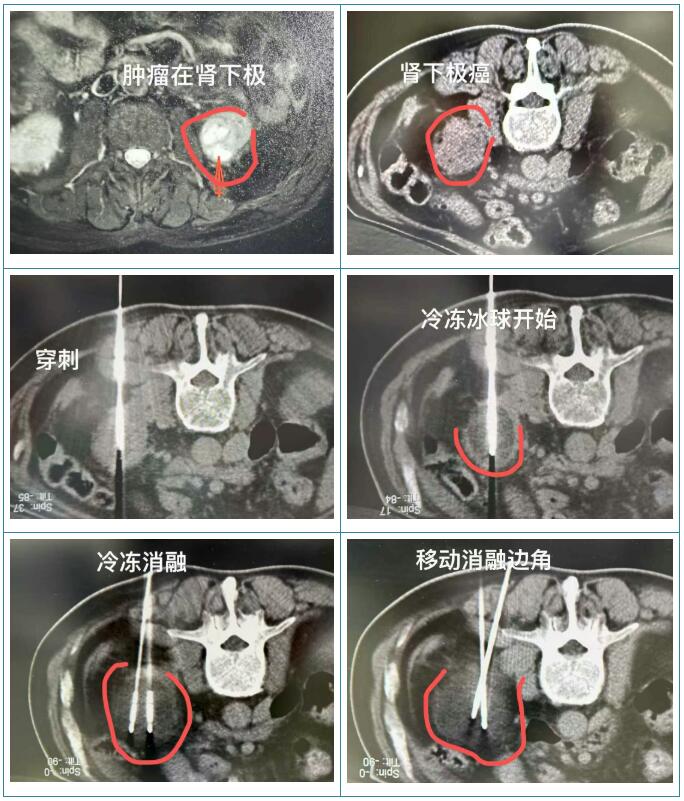

面对肿瘤与血液疾病并存的复杂情况,医疗团队经多学科评估认为,李叔有明确的减瘤治疗指征,但传统手术风险过高。结合家属的强烈意愿与李叔的身体条件,团队最终制定了“冷冻消融术+术后靶向药物治疗”的个体化方案。冷冻消融能以超低温“冻死”肿瘤细胞,创伤小、恢复快,更适合高龄多病的患者。

“11月18日做冷冻、19日从ICU转普通病房、20日拔掉尿管后,就像个小孩子似的到处溜达,乐呵乐呵跟其他病友唠嗑了。”李叔的女儿告诉我们,父亲的整体状态都非常好,重要是没有太明显的疼痛感,吃饭睡觉也没影响到,她们都十分满意。